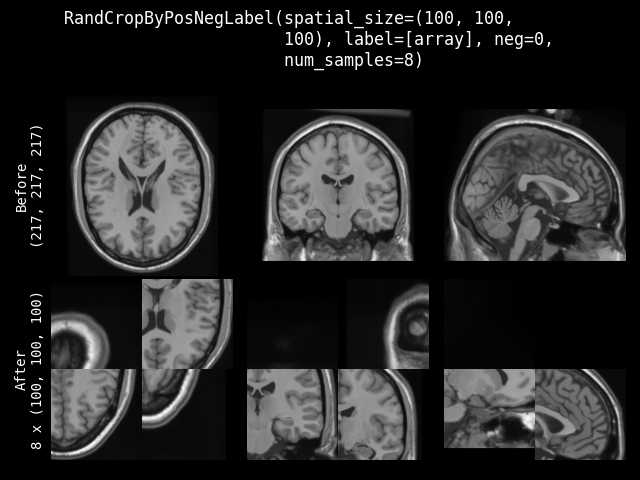

RandCropByPosNegLabelseems not correct(it's not 8 samples, and why some black regions?):

@Nic-Ma , and you're right. There's something wrong with all the num_samples=8, I'll check that. |